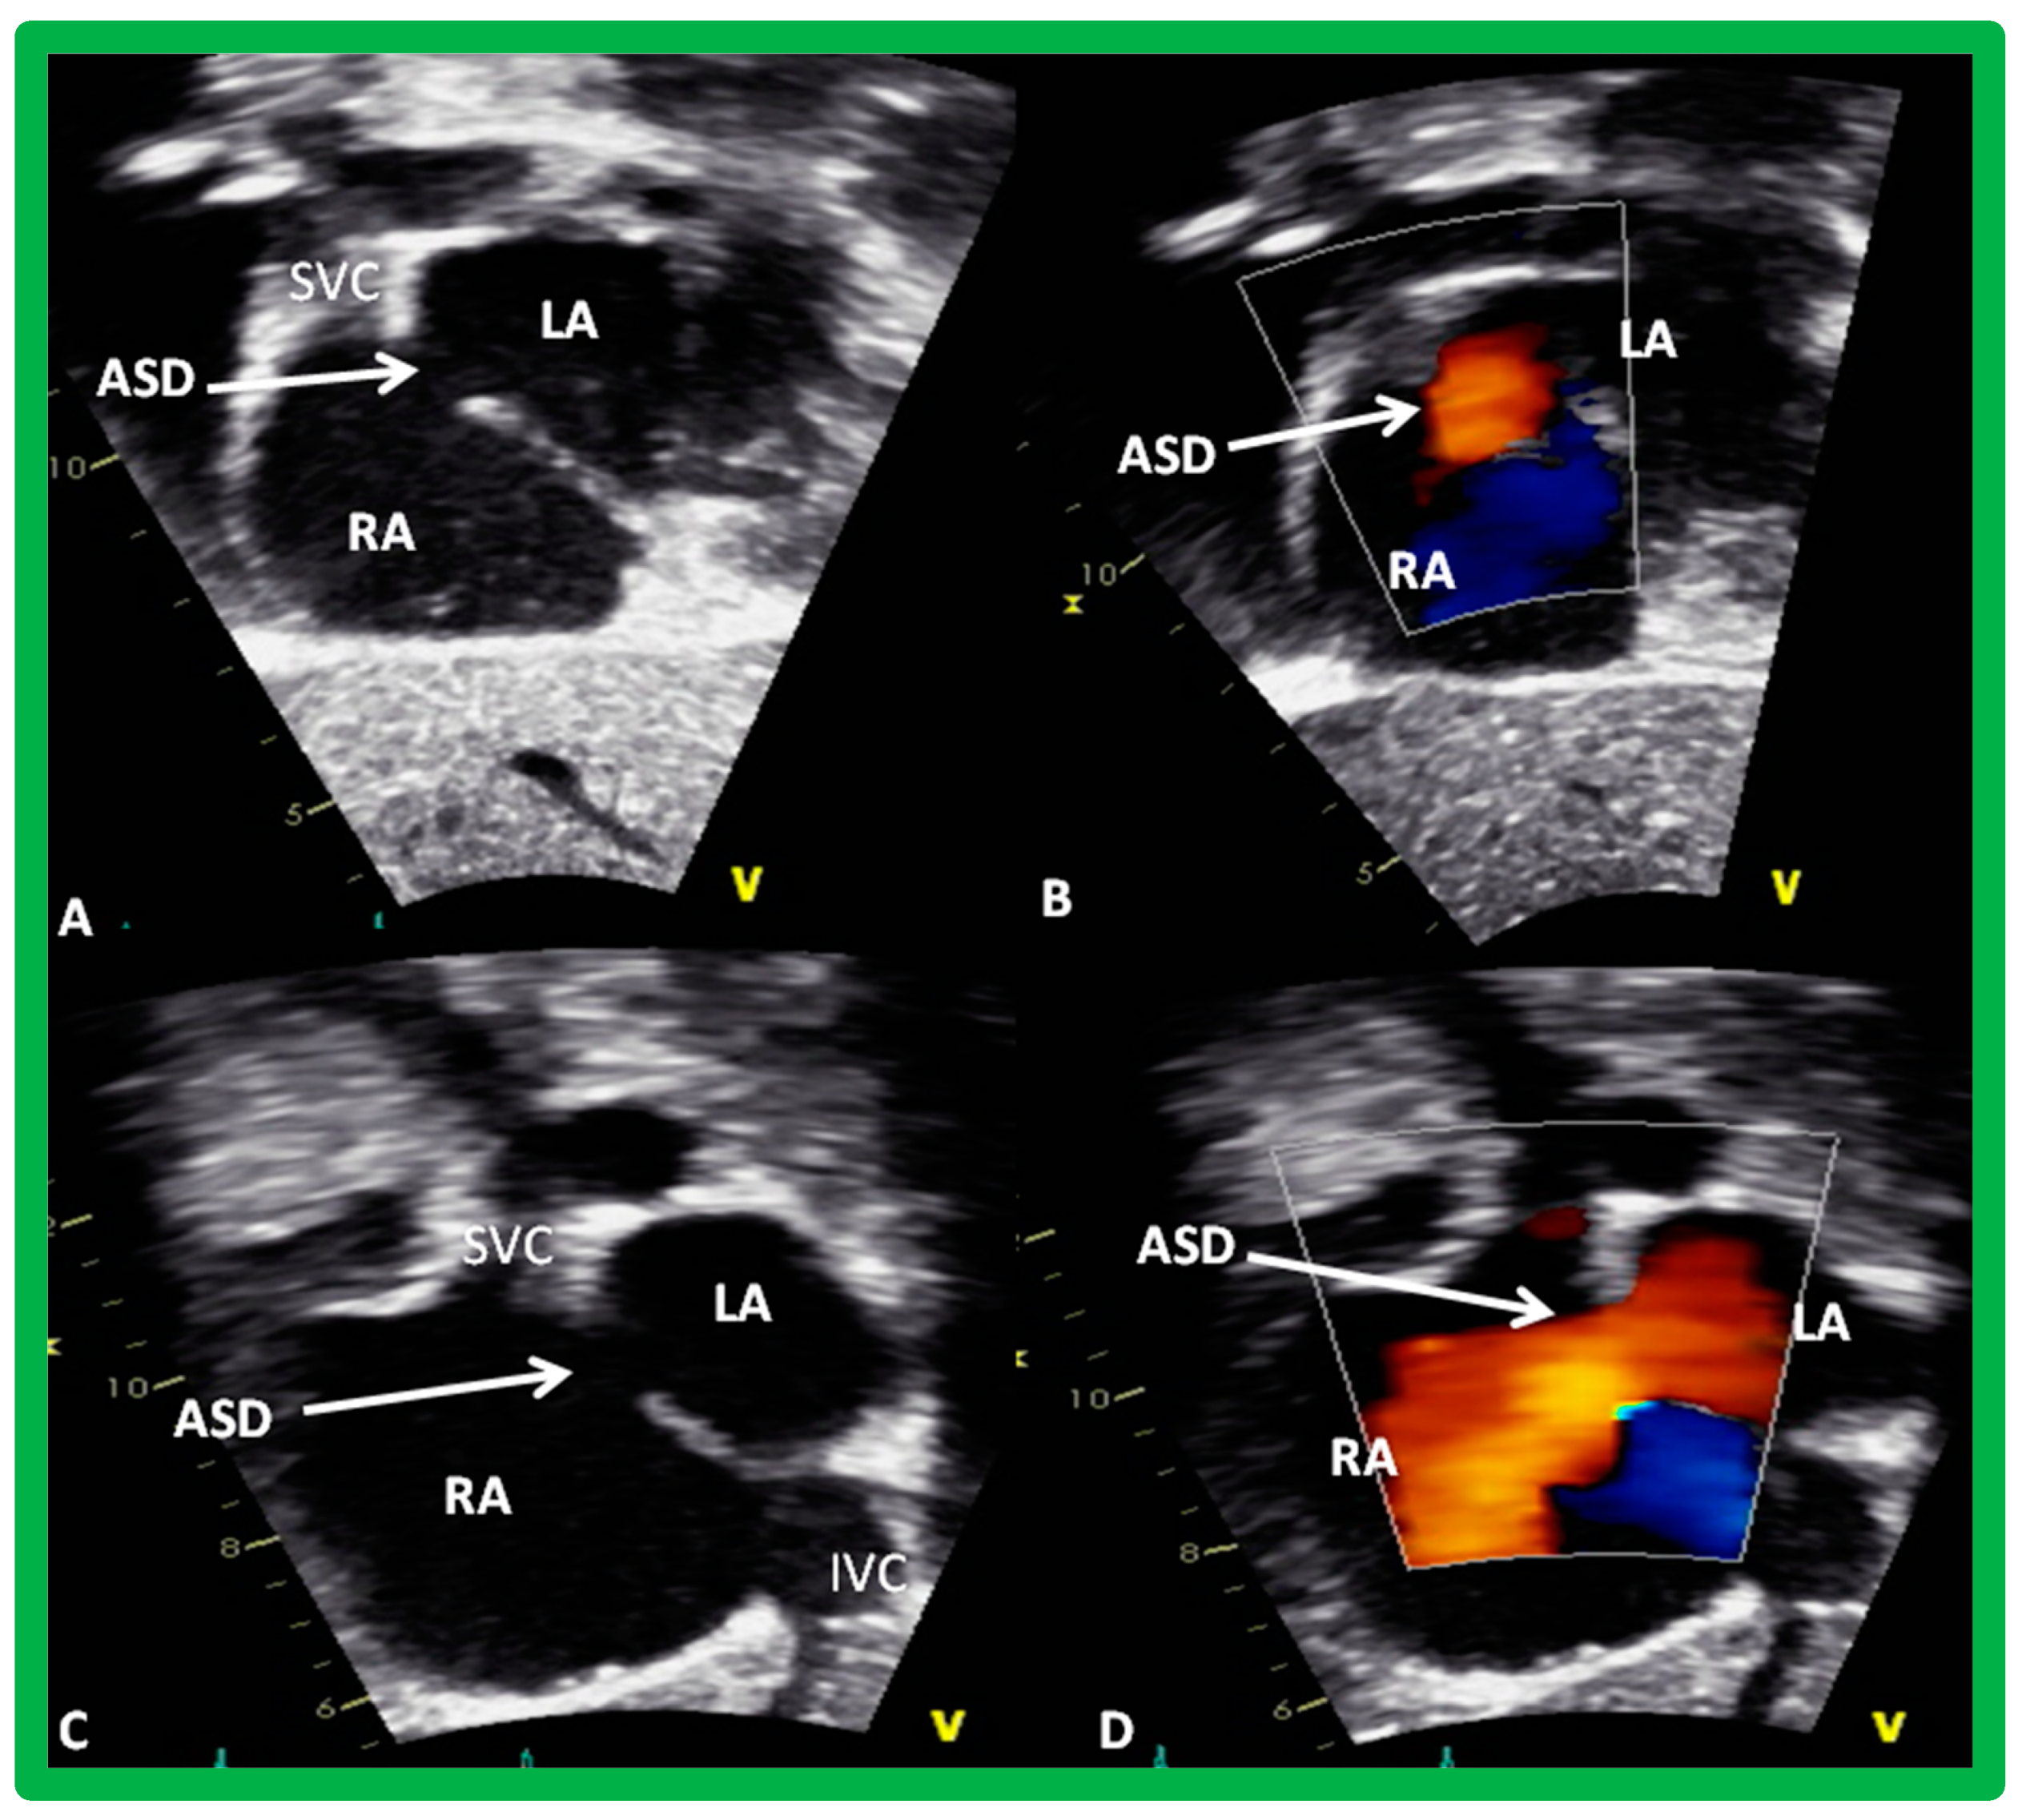

6. TEE and ICE